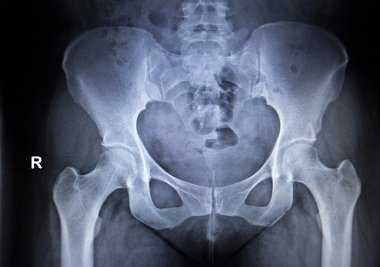

Измерения при обследовании тазобедренных суставов.

(а, б) Убедитесь, что пациент прямо лежит на кушетке для осмотра, что таз его расположен абсолютно ровно,

т. е. что передние верхние ости расположены на одном уровне по отношению к продольной оси тела.

(в) Найдите внутренние лодыжки. (г) Разница в длине ног будет, как правило, очевидна.

(д, е) Длину ног можно наиболее точно определить, измерив расстояние от передней верхней ости до внутренней лодыжки с обеих сторон.